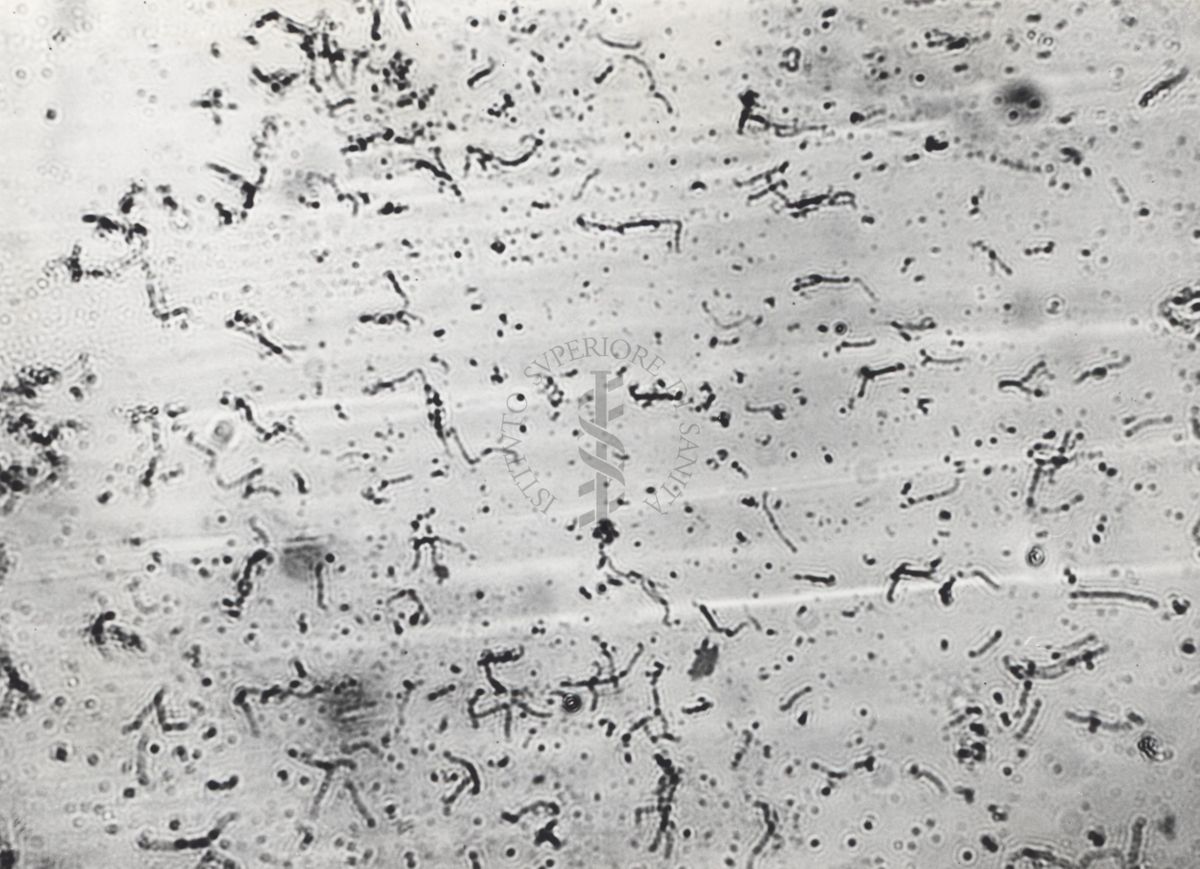

Leptospire agglutinazime

Roma, 02 febbraio 1962

MIC.01901-01904